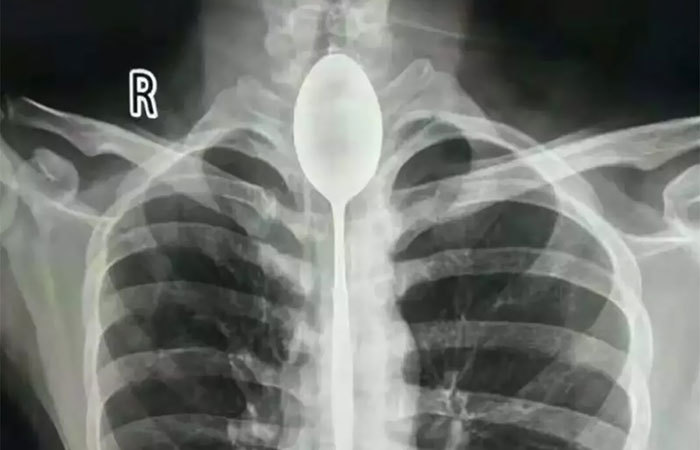

文章插图

吞下一个勺子的x射线